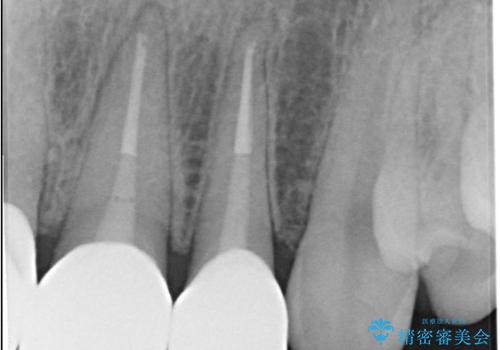

オールセラミックは、光の透過性が天然歯に非常に近いため、周囲の歯と見分けがつかないほどの透明感と自然な色調を再現できます。また、プラークが付着しにくく、金属アレルギーの心配もありません。

緻密な色合わせと形態調整を重ねた結果、長年のコンプレックスであった前歯の欠けや変色が解消。機能性と審美性が完璧に調和した、自信を持って笑える美しい口元を実現することができました。